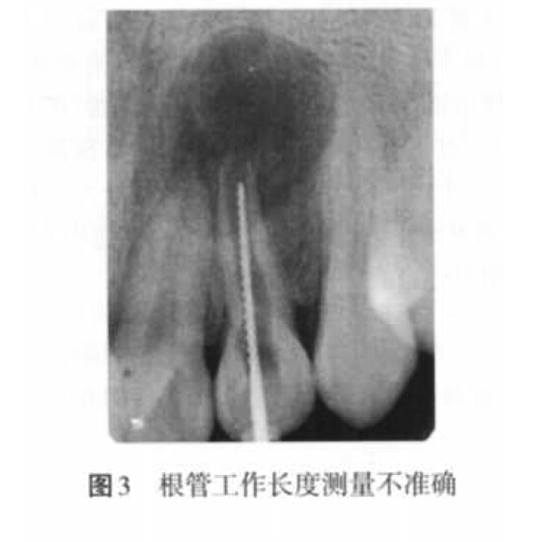

(2)超充原因:主要包括預(yù)備成形不良、根尖孔大而主牙膠尖過小(圖4)、根管工作長(zhǎng)度測(cè)量不準(zhǔn)確、根充技術(shù)選擇不當(dāng)以及術(shù)者操作不當(dāng)?shù)仍颉?p style="text-align:center">